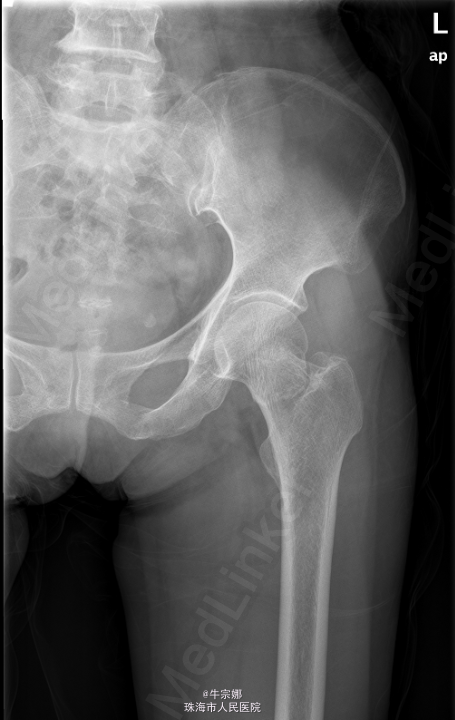

患者,女,65岁,因“外伤致左髋部疼痛伴活动受限10小时”入院。10小时前患者劳动时时不慎向后摔倒,左髋部、左肘部着地,当即感左髋部疼痛,活动受限.

左髋部皮肤完整无淤青,周围软组织无明显肿胀,局部压痛存在,左髋关节活动受限,腹股沟及鞍区感觉无明显减退,轴向叩击痛(+),左下肢无外旋畸形及短缩畸形. 2015-05-22本院CR :左股骨颈骨折. CT:左股骨颈骨折。